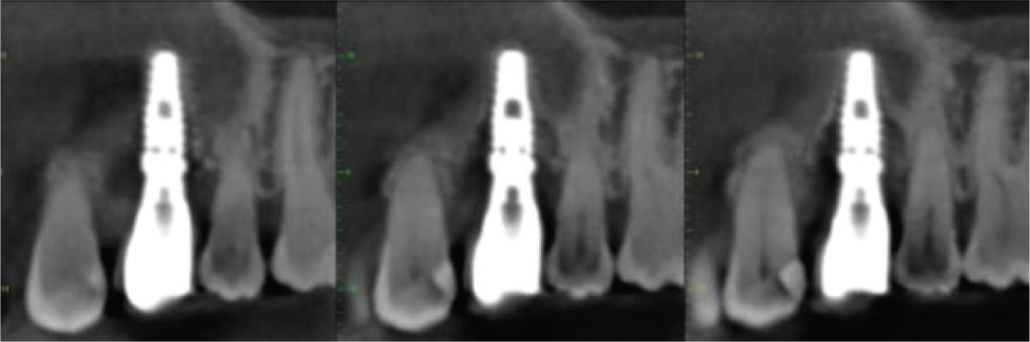

The implant shows definitive signs of failure. There are mesial, palatal and distal vertical bone defects over the coronal half of the implant and a thin radiolucent space around the apical half of the implant on those surfaces. The buccal side of the implant appears denuded of bone, although it is possible that there is some thin bone that the scan is not revealing. There is no point at which osseointegration can be inferred (images 2, 3 and 4).

Image 2. Mesio-distal cross sections of UL4 implant

Image 3. Bucco-palatal cross sections of UL4 implant